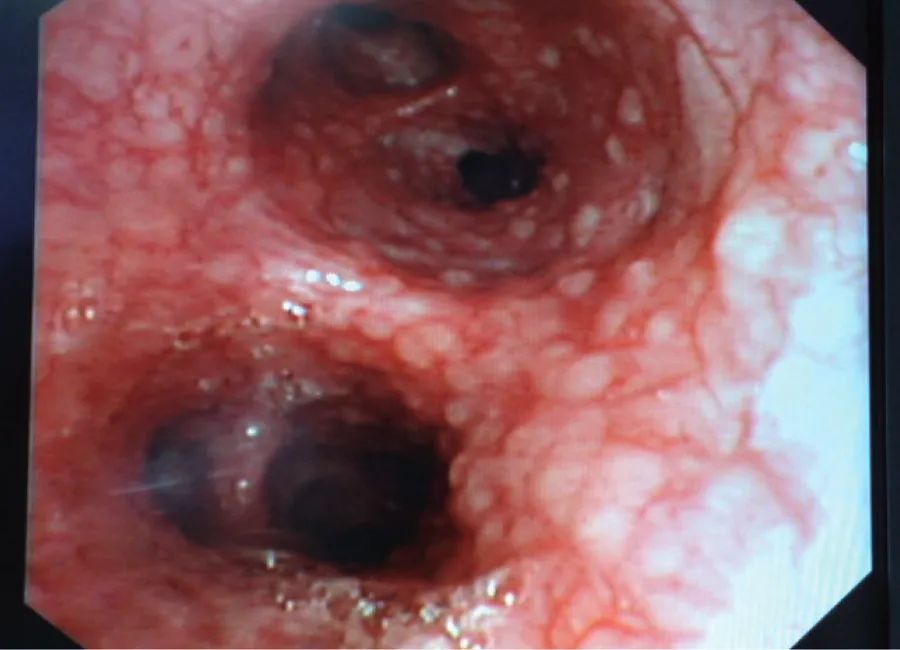

支气管镜所见

支气管黏膜粟粒性结核